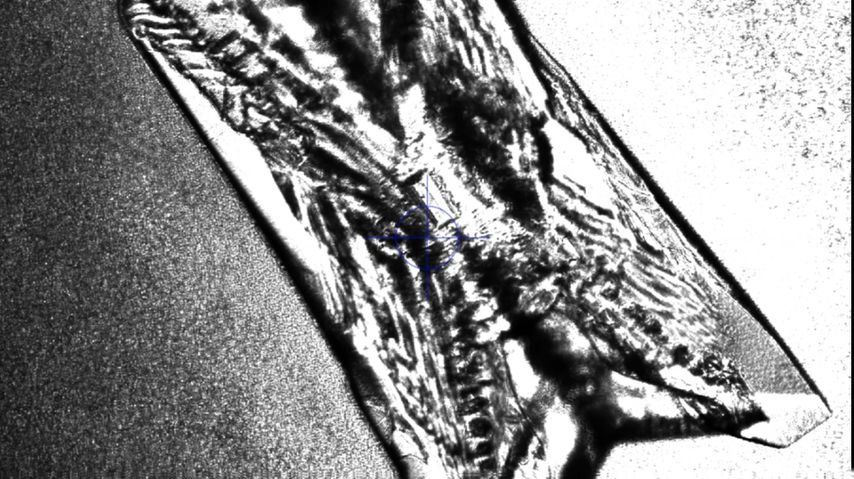

In Gegenwart von Urease produzierenden Bakterien wird Harnstoff im Urin zu Ammoniak und Kohlendioxid gespalten. Durch die Ammoniak- und CO2-Produktion und die darauffolgende Reaktion von CO2 mit H2O, die zu hohen Bicarbonatwerten führt, steigt der Urin-pH-Wert stetig an und pendelt sich schließlich bei 7,2–8,0 ein. Ammoniak wird dabei weiter hydrolysiert und bildet Ammoniumionen. Die basische Übersättigung des Urins führt bereits ab Urin-pH-Werten von 6,8 zu einer erhöhten Kristallisationsneigung von Kalziumphosphat zu Carbonatapatit. Zusätzlich kristallisiert im basisch übersättigten Urin ab einem Urin-pH-Wert >7,2 das basisch nur schwer lösliche Magnesium mit den Ammoniumionen zu Magnesiumammoniumphosphat (Struvit). Es bildet sich „Struvit-Apatit-Staub“ um die Urease produzierenden Bakterien. Sowohl in diesen Bakterien als auch in ihrer Umgebung kann es zur Kristallisation kommen. Die in den Bakterien gebildeten Mikrolithen können nach der Bakteriolyse den Grundstein für die Bildung von neuen Infektsteinen legen (Abb. 1 und 2).2,5

Abb. 1: Mikroskopische Darstellung eines Struvitkristalles durch Anzüchtung von Proteus mirabilis in artifiziellem Urin. Quelle: eigene Forschungsarbeit